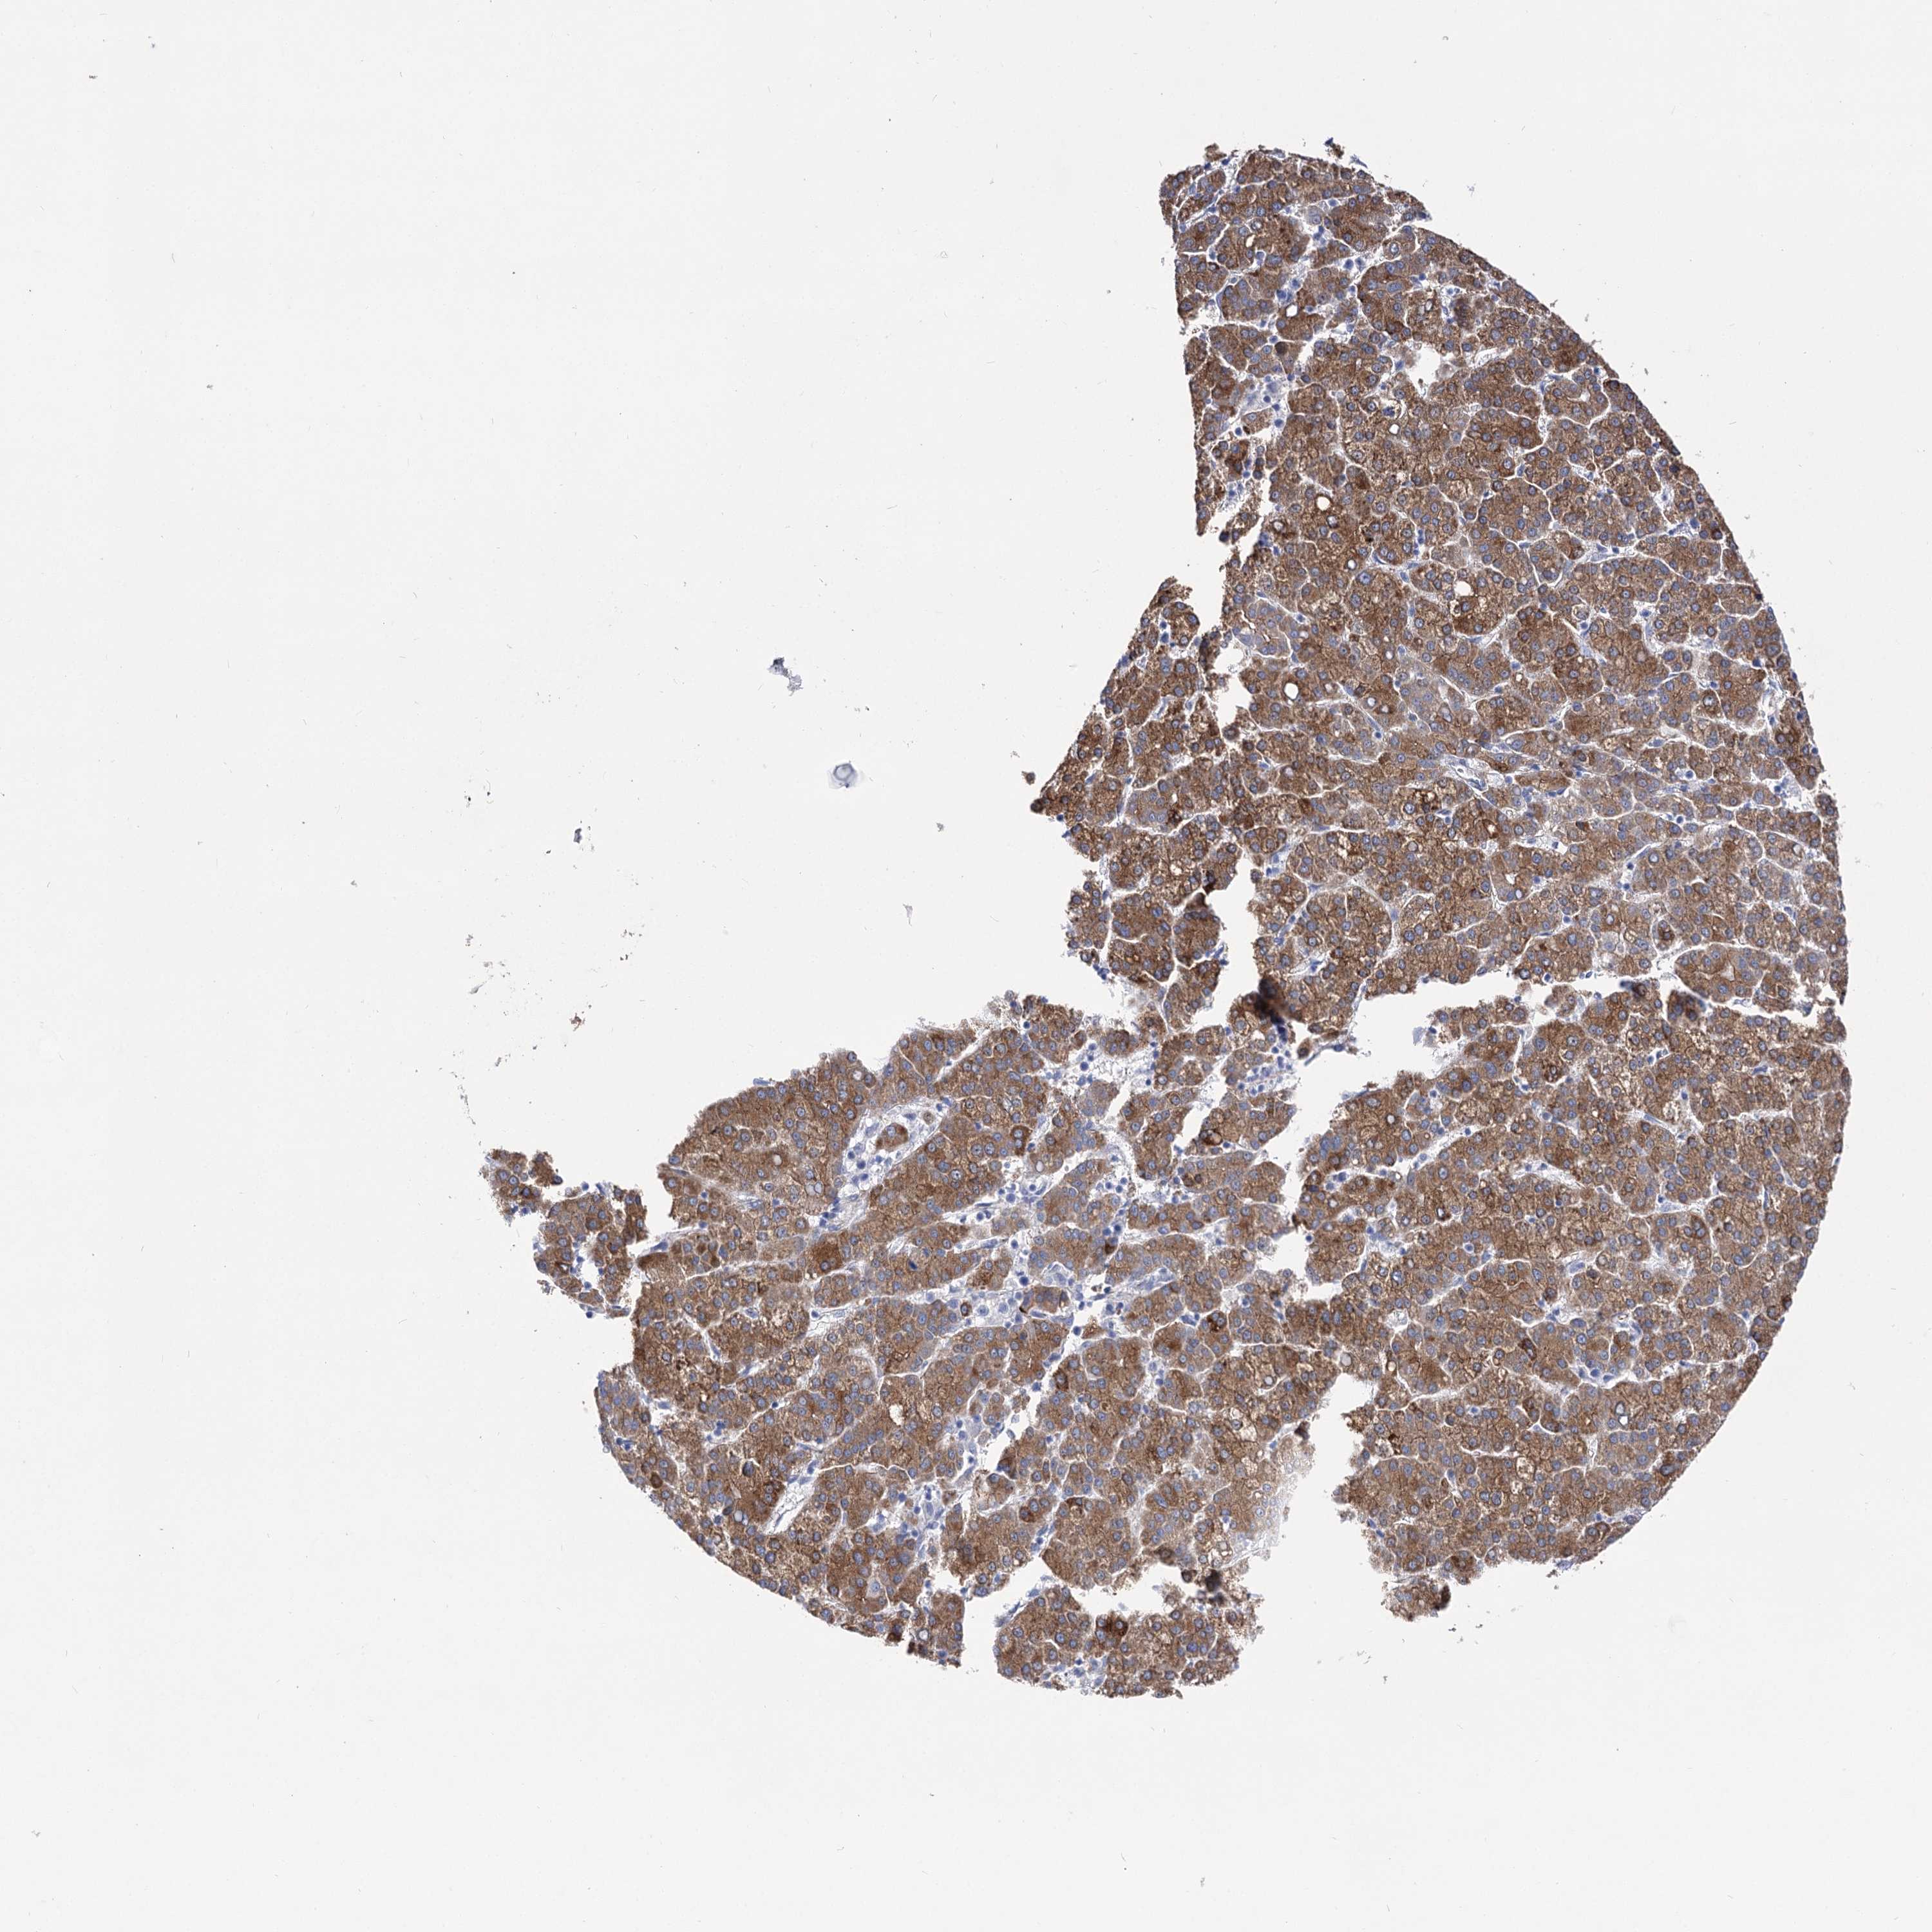

LIVER CANCER - Protein expressioni

A mouse-over function shows sample information and annotation data. Click on an image to view it in a full screen mode. Samples can be filtered based on level of antibody staining by selecting one or several of the following categories: high, medium, low and not detected. The assay and annotation is described here.

Note that samples used for immunohistochemistry by the Human Protein Atlas do not correspond to samples in the TCGA dataset.

Antibody stainingi

Antibody staining in the annotated cell types in the current human tissue is reported as not detected, low, medium, or high, based on conventional immunohistochemistry profiling in selected tissues. This score is based on the combination of the staining intensity and fraction of stained cells.

Each image is clickable and will lead to virtual microscopy that enables deeper exploration of all samples and also displays staining intensity scores, fraction scores and subcellular localization as well as patient and tissue information for each sample.

Antibody HPA037953

Antibody HPA037954

Staining

High

Medium

Low

Not detected

Intensity

Strong

Moderate

Weak

Negative

Quantity

>75%

75%-25%

<25%

None

Location

Nuclear

Cytoplasmic/membranous

Cytoplasmic/membranous,nuclear

Cholangiocarcinoma

Carcinoma, Hepatocellular, NOS